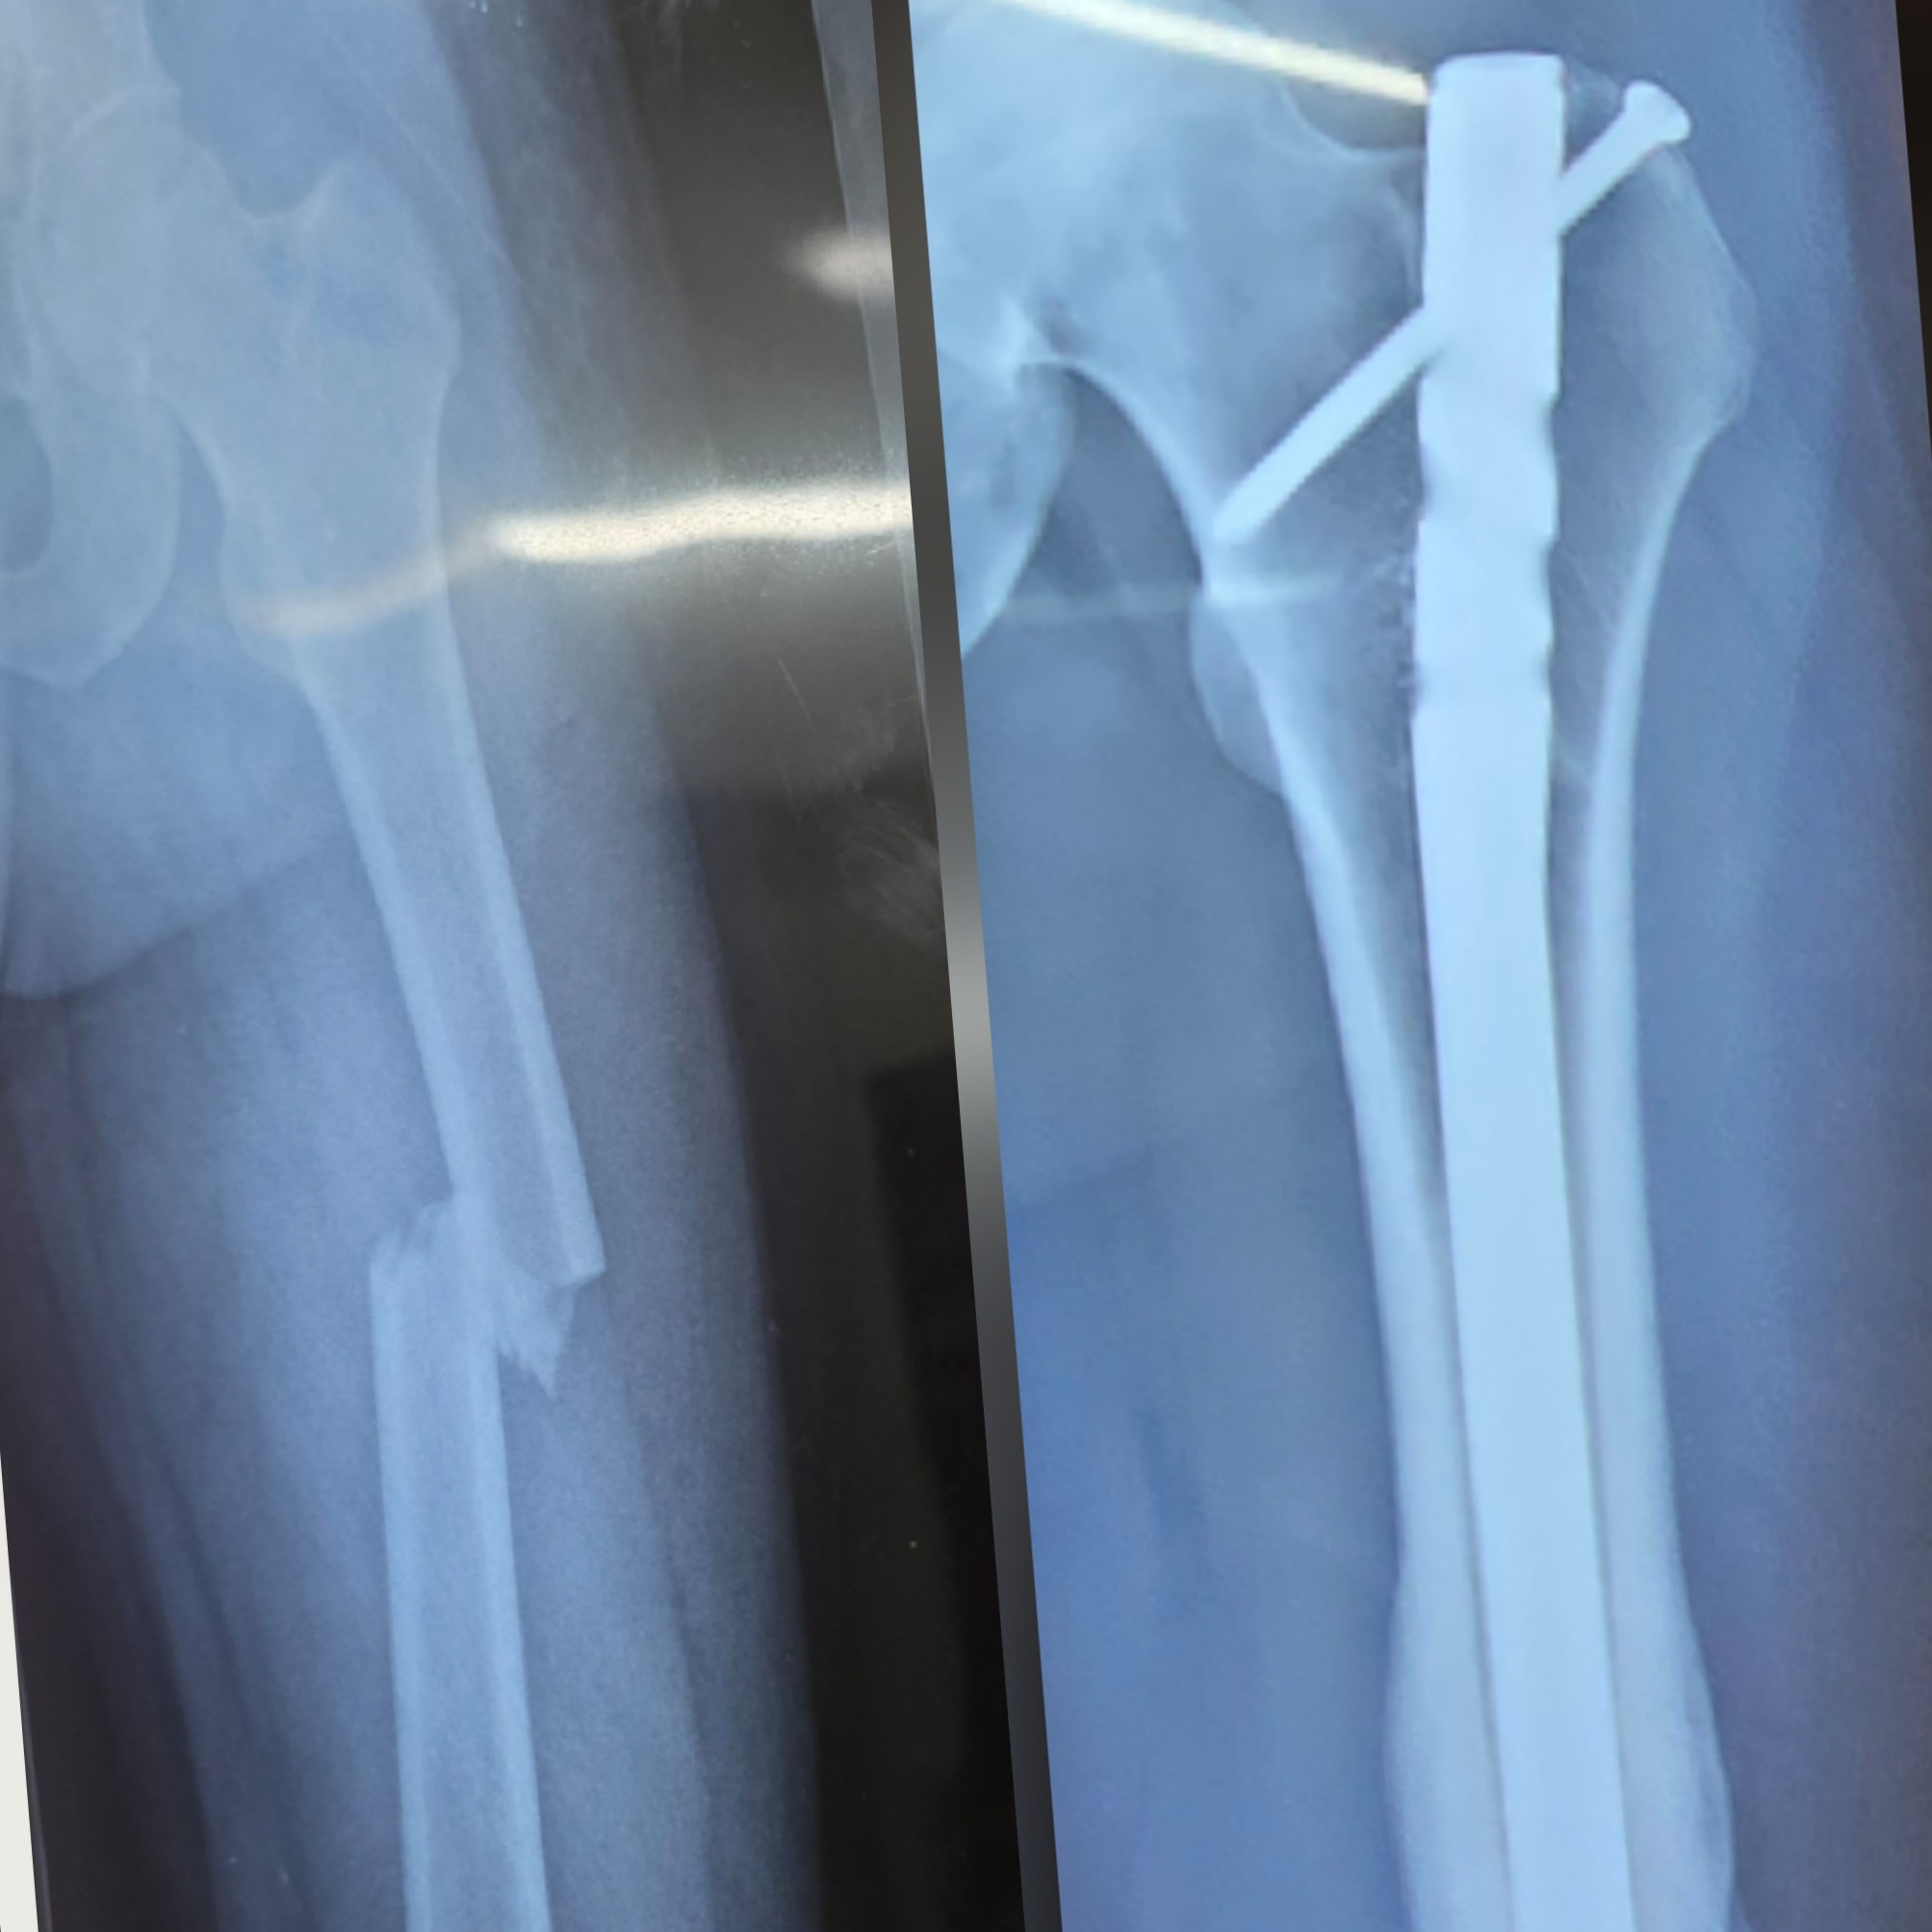

Dr Abhishek Kumar Orthopaedic Clinic LG 22 La Residentia Tech zone 4, Greater Noida west, Uttar Pradesh 201308 +918042753310 Hi.drabhishekkumar@gmail.com